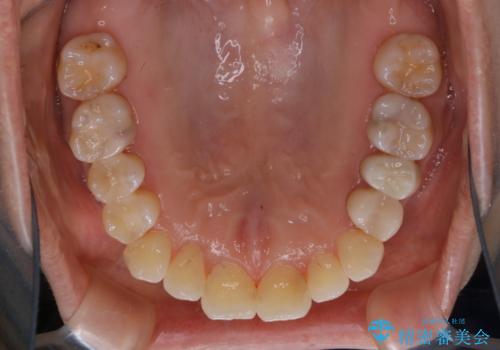

矯正治療とセラミック治療が終了後のPMTC

- 矯正治療とセラミック治療の総合治療が終了したため、クリーニングをしっかりとしてからメンテナンスに入りたいとのことでした。PMTC30分コースを行いました。

矯正治療が終わり、せっかくきれいになった歯並びも、虫歯・歯周病などになってしまっては元も子もありません。

矯正治療やセラミックなどによる被せ物の治療終了のタイミングではクリーニングを行い、汚れや着色の除去、歯と歯の間・歯と歯肉との境目などのケアをしっかりすることをおすすめしています。

ご自身での歯ブラシ・セルフケアを行うと同時に、定期的なクリーニング(PMTC)を行うことで、いつまでも健康な歯を保つことができます。